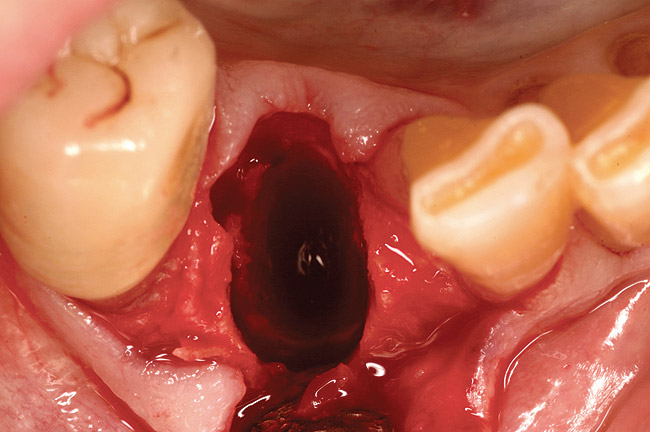

Thirty patients were selected on the basis of need for dental extractions with bone preservation and/or augmentation in the socket before the placement of a dental implant. These patients were cleared medically for oral surgical procedures. Preoperative clinical photographs and periapical radiographs were taken. After administration of local anesthesia, full-thickness labial and lingual/palatal flaps were elevated. Minimal soft-tissue manipulation was performed to allow visualization of the entire alveolar crests and debridement of fenestrations and/or dehiscence defects, if present. Elevation of each tooth or retained roots was performed, using periotomes, luxatomes, proximators, root forceps, and any other instruments and procedures as required to extract the tooth with minimal trauma (Figure 1). After extraction and thorough debridement of the socket by mechanical means, clinical photographs were taken. The sites then were grafted with a resorbable β-TCP of small particle size, 150 µm to 500 µm (Cerasorb) (Figure 2). This material has been used and reported in the literature for almost 30 years as a viable bone graft in orthopedic and other surgical specialties. In this study, the granules of β-TCP were mixed thoroughly with blood from the surgical sites and the sockets filled to ideal contours faciolingually and apicocoronally. The grafts and adjacent 3 mm of alveolar bone then were covered with resorbable collagen barriers (BioMend®, www.zimmerdental.com) (Figure 3). The flaps were repositioned and the areas closed with an appropriate number and type of sutures. No attempts were made to obtain primary closure over the exposed barriers. Postoperative radiographs and clinical photographs were taken. Subsequently, sutures were removed at 1 to 2 weeks.

Figure 1  Occlusal view after extraction of tooth No. 27 using Piezosurgery<sup>®</sup> (Piezosurgery Inc, www.piezosurgery.com) and thin-bladed elevators.

Figure 1

Figure 12  A patient who had tooth No. 2 extracted using Piezosurgery, periotomes, thin-bladed elevators, and small-beaked forceps, enabling preservation of all bony peaks.

Figure 12